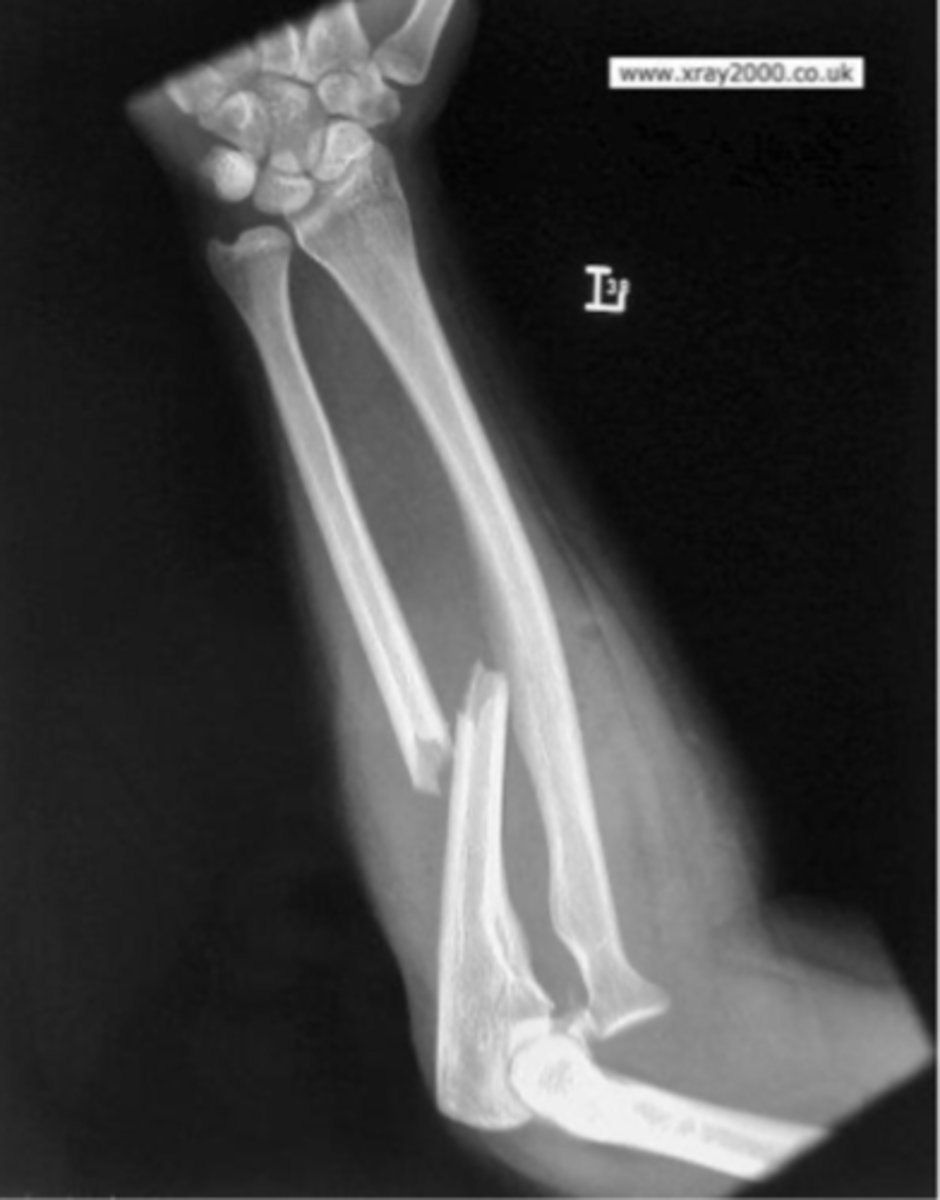

Monteggia's fracture

What is the issue?

AP forearm

What view is this?